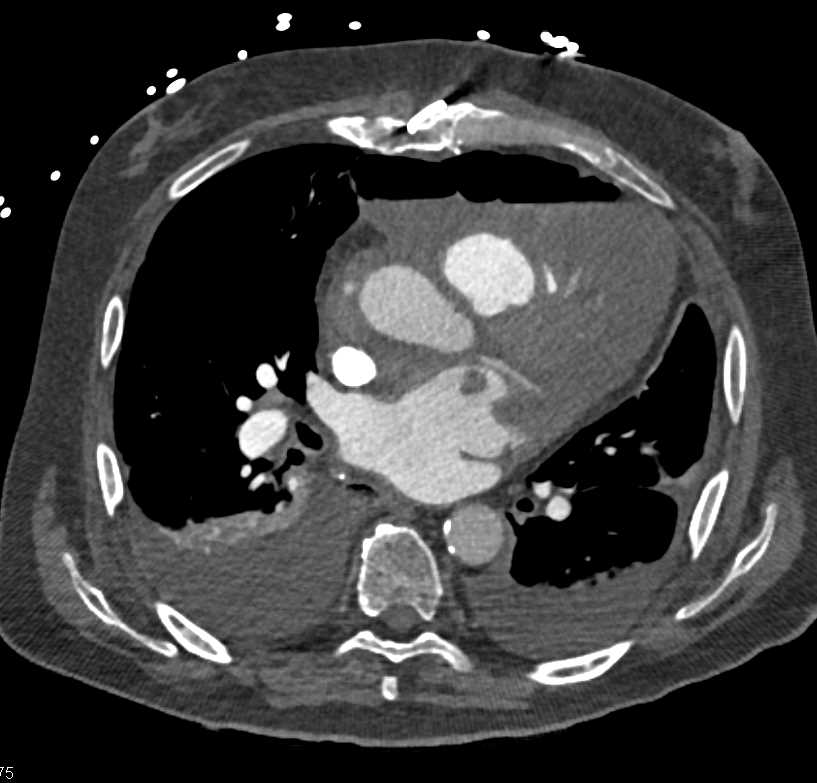

Post Cardiac Surgery Changes